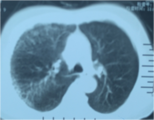

Случай А

Пациент, мужчина, 80 лет

Ход болезни: перерывный кашель, отхаркивать мокроту 30 лет, ход болезни усилился и повышенная температура в 1 неделю.

Терапия : Хронический астматический бронхит (острый срок наступления) вместе с обструктивной эмфиземой и лёгочном заражением, и появилась гипопротеинемия дистрофии. Врачи провели соответствующую фармакотерапию и парентеральное питание. После 10 дней клинический симптом улучшился. Проведя вторичную проверку, основные показатели состояния организма нормальные и без аномалии.